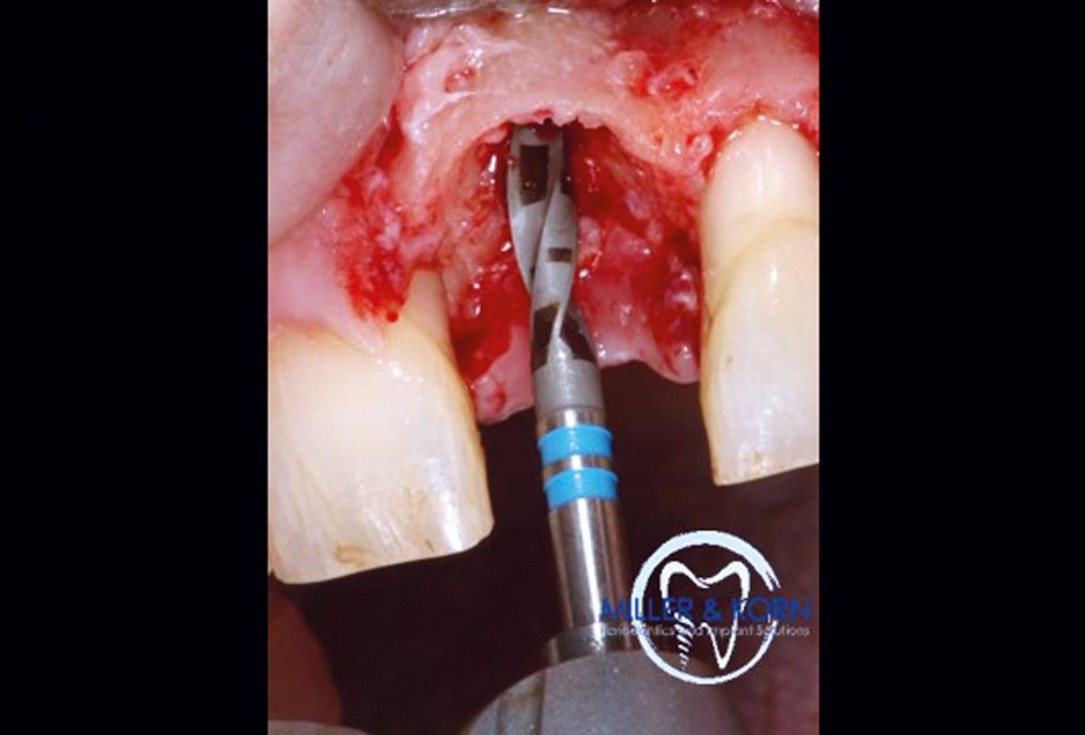

18/39 - Preparation of the implant bed using a 2.8 mm twist drillImmediate implant placement and correction of horizontal and vertical bone loss using an allograft bone ring, cerabone® and Jason® membrane - Drs. Miller and Korn